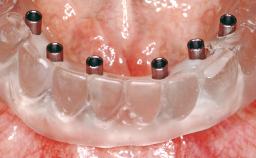

Immediate Loading of Six Implants in the Maxilla and Final Restoration with a Full-Arch CAD/CAM Zirconia FDP

Modality 6+ implants with immediate loading

Loading Protocol Immediate